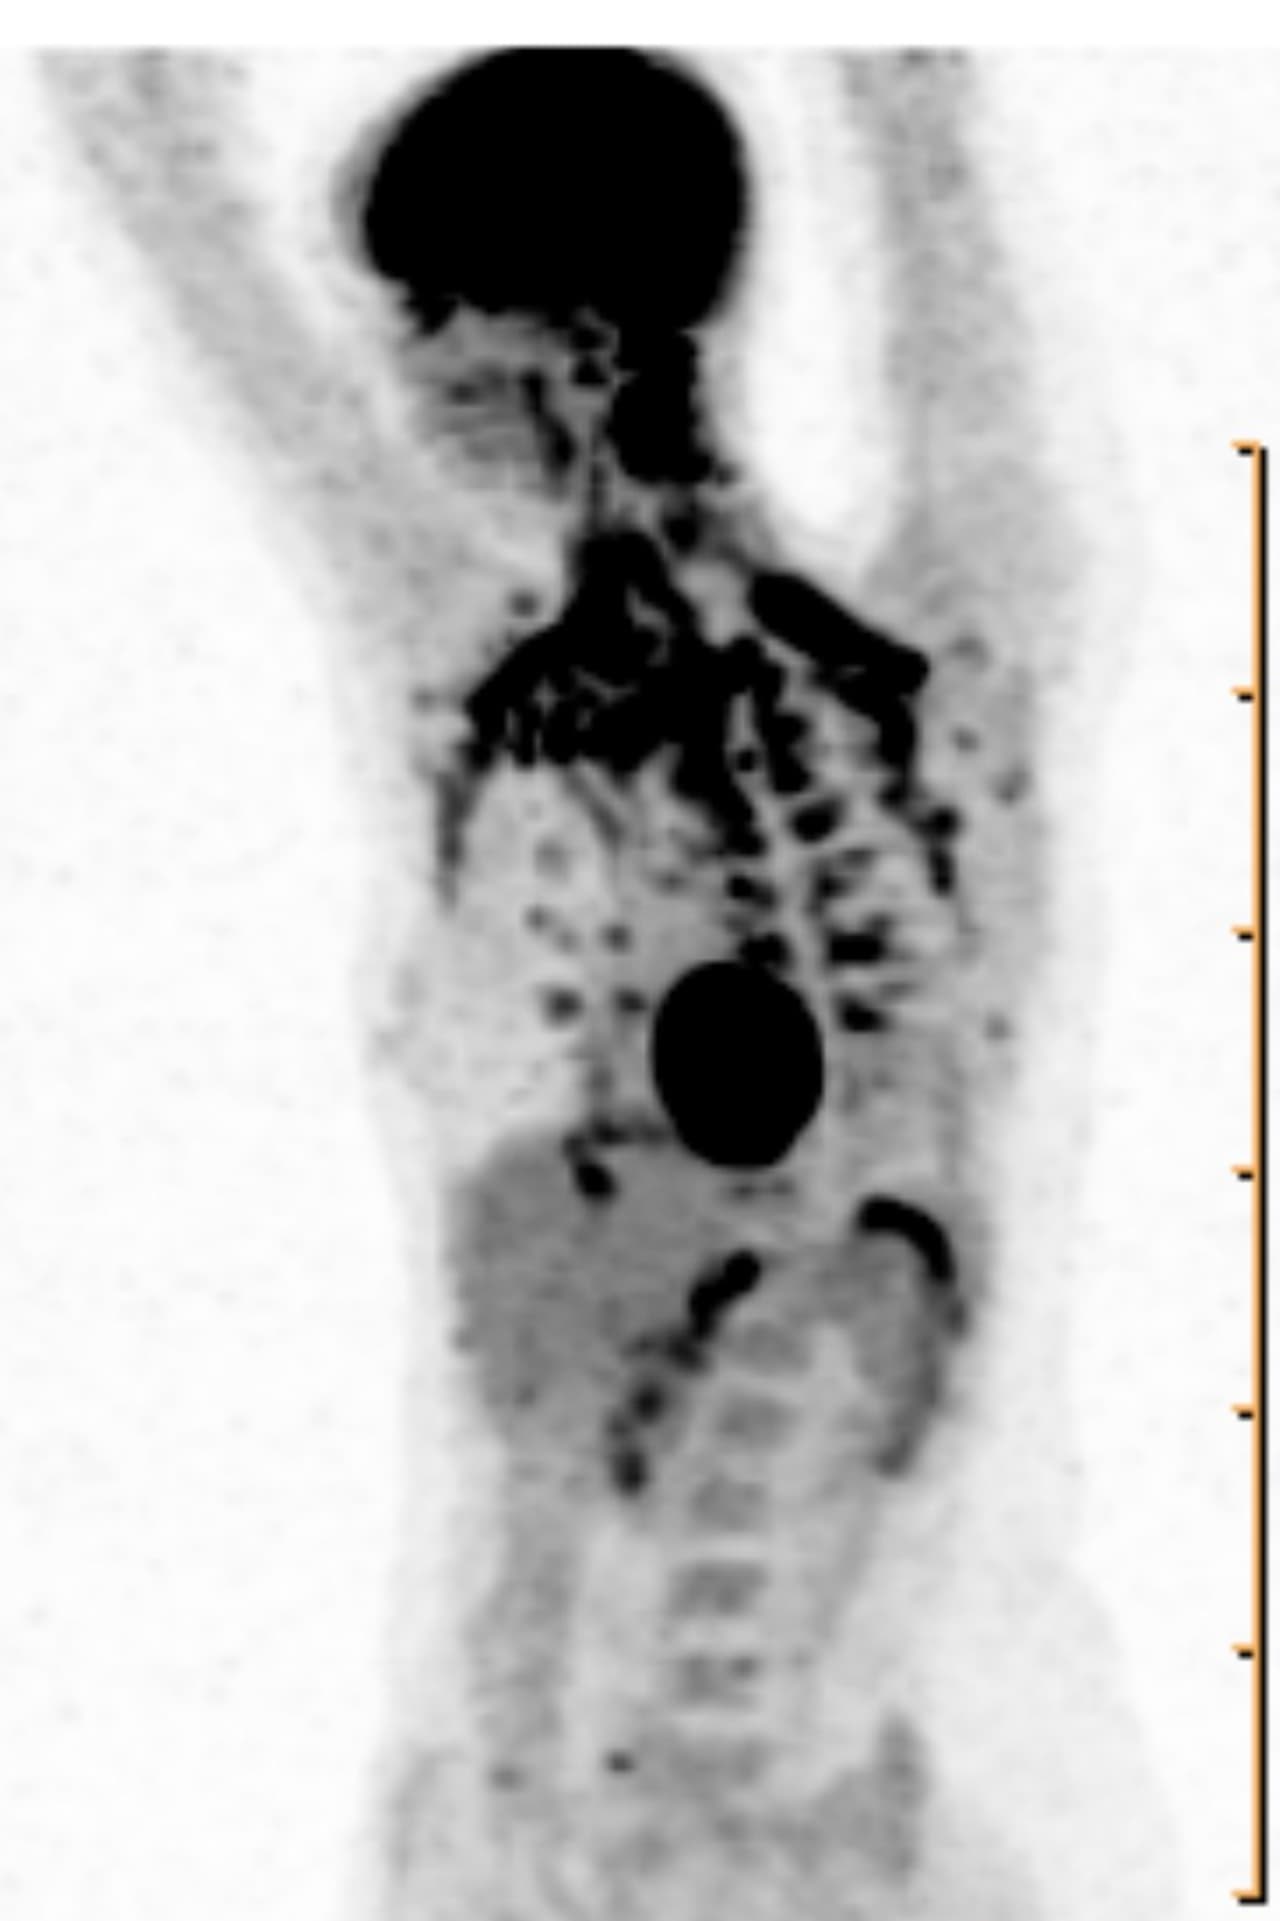

Гиперфиксация рфп при пэт кт

Гиперфиксация рфп при пэт кт 140 фото